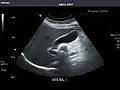

Renal ultrasonography

Ultrasonography of the kidneys is essential in the diagnosis and management of kidney-related diseases. The kidneys are easily examined, and most pathological changes in the kidneys are distinguishable with ultrasound.[7]

Right kidney